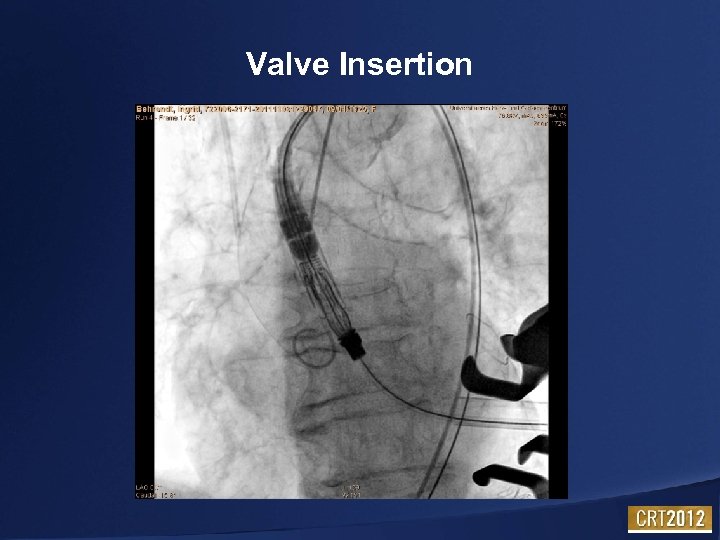

Valve Insertion